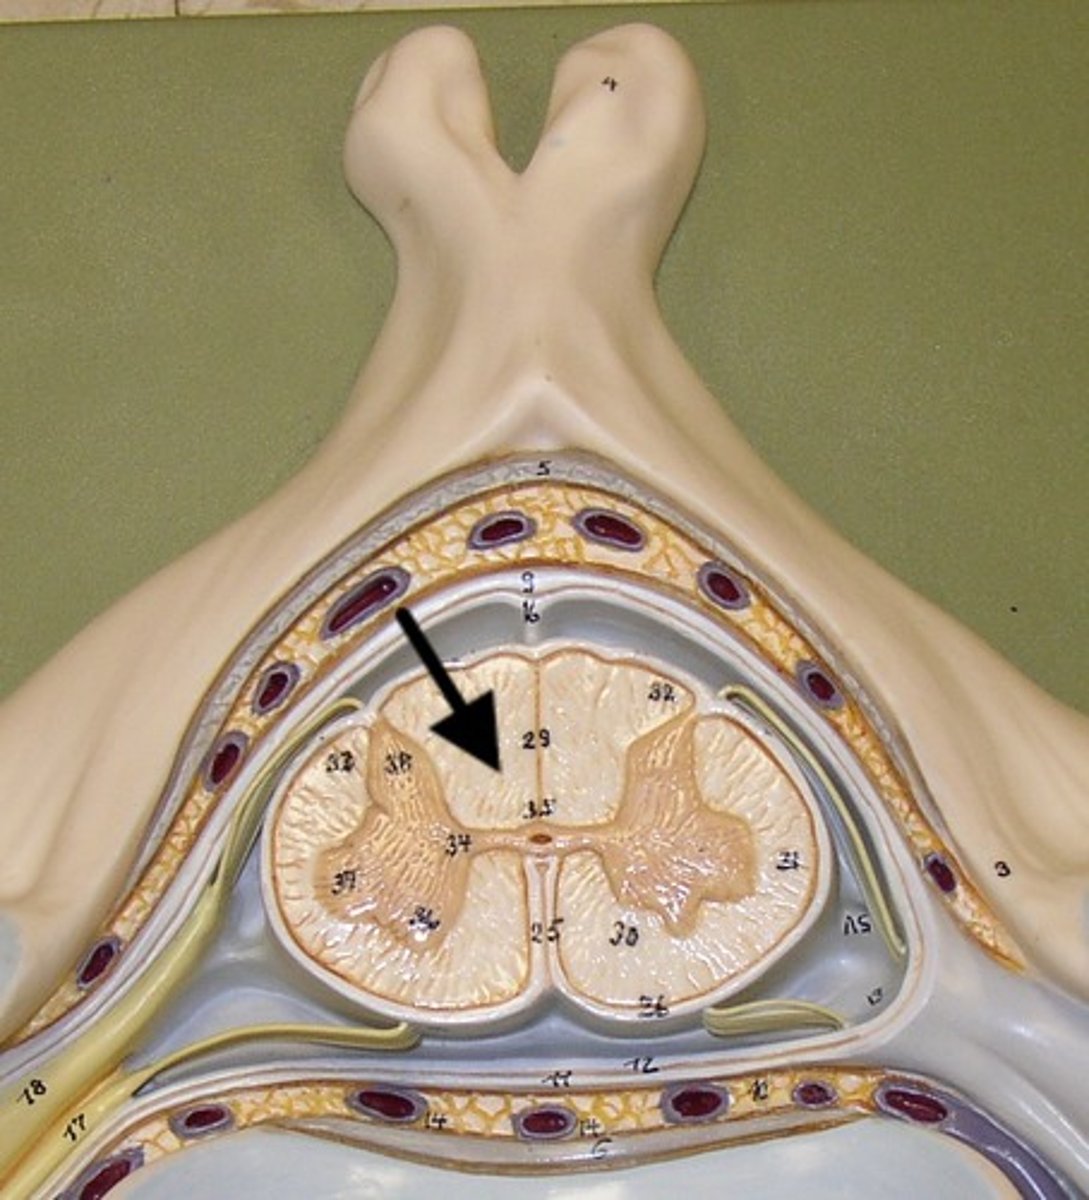

grey matter

(in orange)

dorsal horn

lateral horn

ventral horn

dorsal median sulcus

ventral median fissure

grey commissure

central canal

white matter

dorsal column

lateral column

ventral column

meninges

three protective membranes that surround the brain and spinal cord (AKA: the "maters")

pia mater

thin, delicate inner membrane of the meninges

arachnoid mater

middle layer

dura mater

Outermost layer of the meninges

denticulate ligament

subarachnoid space

contains cerebrospinal fluid

lateral corticospinal tract

dorsal root ganglion

ventral root